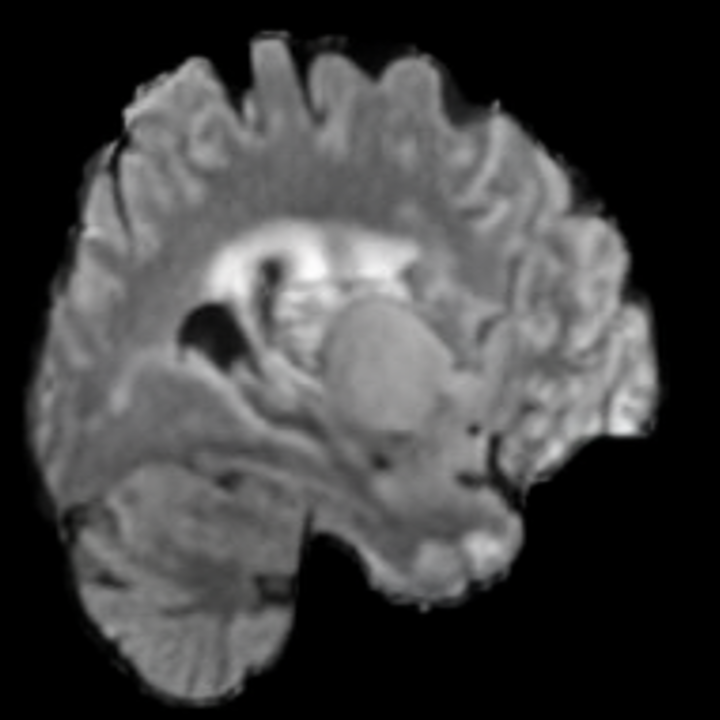

6.3 When does X-Diffusion Fail?

To see when and how X-Diffusion fails, we conducted an experiment on healthy brains (no tumour) using IXI dataset, by running an X-diffusion trained on BRATS brain tumor dataset. Our X-Diffusion achieved a PSNR of 35.86 dB on the IXI dataset despite being trained on the BRATS dataset. We then ran the tumour segmenter on the set of 582 healthy scans and corresponding generated MRIs. The segmenter predicted tumours in 9.9% of the real healthy brains and in 11.3% of the generated brain MRIs. Some of these tumor hallucination examples fron X-Diffusion generation are shown in Figure 10.